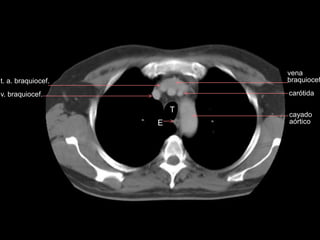

vena

braquiocef

T

E

cayado

aórtico

carótida

t. a. braquiocef.

v. braquiocef.